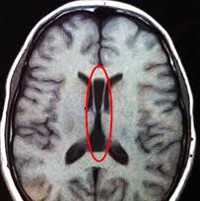

Характерным анатомическим изменением является колпоцефалия, при которой расширены задние отделы боковых церебральных желудочков. Состояние не относится к истинной гидроцефалии новорожденных, а обусловлено уменьшением кортикальных ассоциативных путей. Еще один типичный признак порока — пучки Пробста, представляющие собой неправильно ориентированные аксоны, расположенные параллельно межполушарной щели.

- КТ головного мозга. При компьютерной томографии определяются широко расставленные передние рога, высокое стояние третьего желудочка, параллельный ход медиальных стенок боковых желудочков. КТ производится в рамках постнатальной диагностики.

- МРТ головного мозга. Для максимально точной визуализации степени агенезии или гипоплазии мозолистого тела новорожденным выполняется магнитно-резонансная томография в трех плоскостях. По показаниям МРТ может рекомендоваться беременным женщинам для исключения несовместимых с жизнью сочетанных пороков ЦНС.